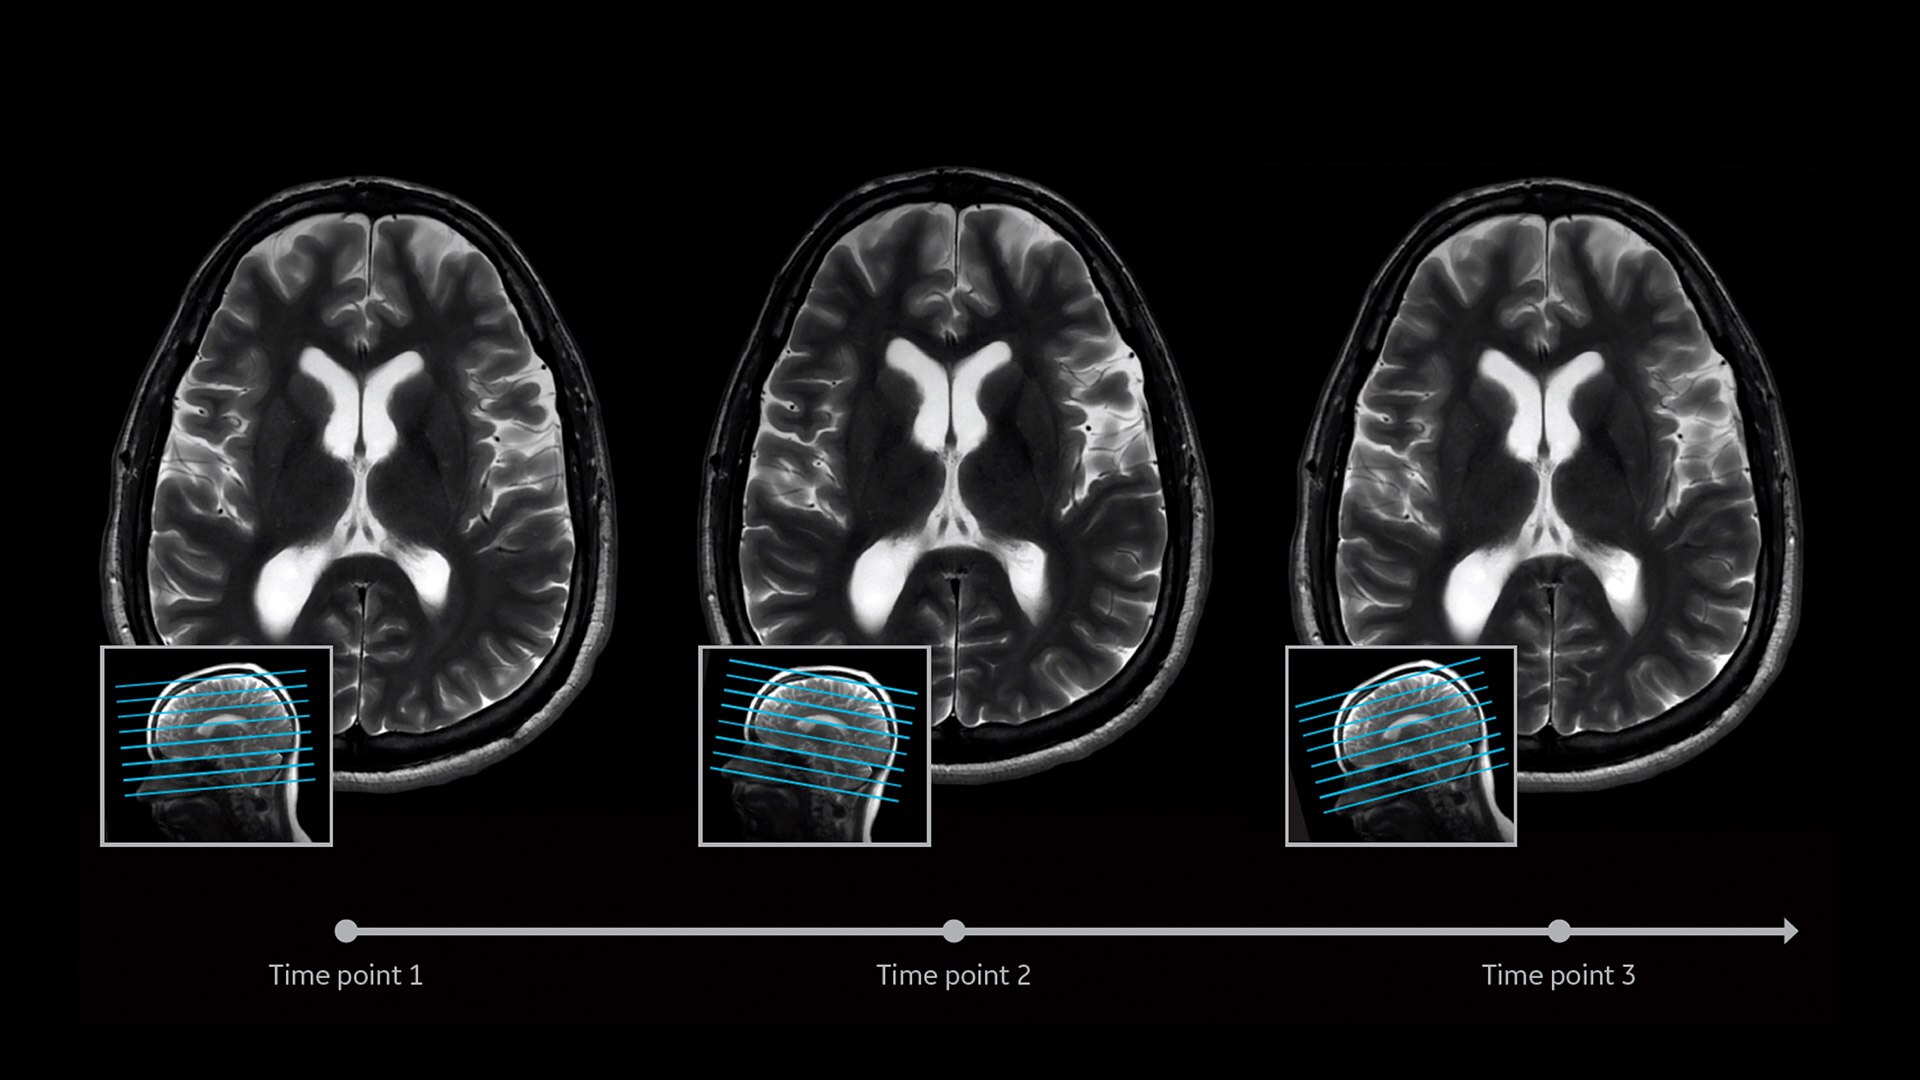

Deliver consistent MRI slice placements across multiple clinical time points, with a deep-learning algorithm that provides efficiency and time savings.

AIR-x feature hero consistent and accurate